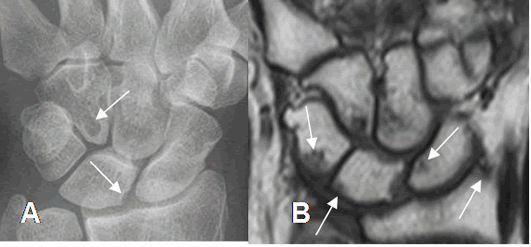

Fig 26. Artropatía reumática.

A: Rx AP. Erosiones del semilunar y el ganchoso.

B: RM coronal en T1. Además de estas erosiones, se aprecian otras en el escafoides, semilunar, piramidal y el radio, no visibles en la Rx inicial.